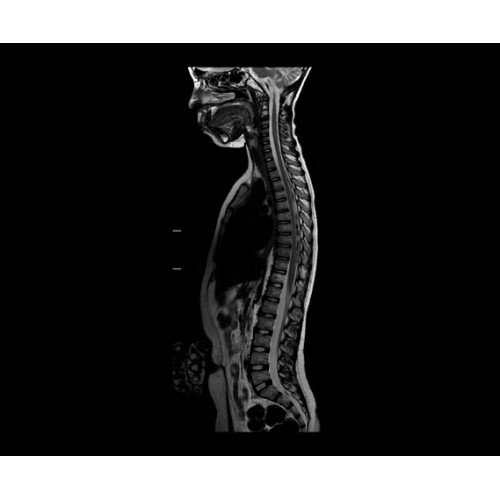

SIGNA PET/MR 3.0T — это гибридная система, в которой совмещаются две принципиально разные технологии — магнитно-резонансную томографию (МРТ) и позитронно-эмиссионную томографию (ПЭТ). Система отличающийся высокой чувствительностью и эффективностью и предназначена для диагностики в области онкологии, неврологии, кардио-васкулярных исследований, исследований воспалительных процессов.

• МРТ с функцией нулевого времени эхо (ZTE) отличается точностью, возможностью персональных настроек и отсутствием ионизирующего излучения. Она приходит на смену традиционному исследованию на основе рентгеновского излучения. МРТ с функцией нулевого времени эхо (ZTE) на базе SIGNA ПЭТ/МРТ является более надежной и быстрой по сравнению с системами, использующими сверхмалое время эхо (UTE).